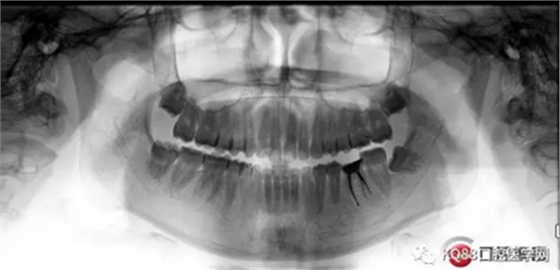

患者:李SW,男,25。

主訴:左下后牙痛一周。

現(xiàn)病史:患者四年前發(fā)現(xiàn)左下后牙蛀牙,未行任何治療,四年間偶爾疼痛,口服消炎藥物緩解,現(xiàn)疼痛加劇,影響進食,來門診就診。

既往史:既往體健,否認心臟病,高血壓,相關(guān)慢性病史,否認藥物過敏史。

??茩z查:頜面部對稱,大張口開口末閉口初清脆彈響,開口型正常,唇舌無麻木,口腔衛(wèi)生良好。36合面大面積缺損,大量黑色腐質(zhì),探出血,舌側(cè)邊緣最低處平齊牙齦緣。36冷診無反應(yīng),叩痛(+)。其他牙無殊。

X-ray:36根尖云霧狀低密度影,根分叉未見異常。

診斷:36慢性增生性牙髓炎。